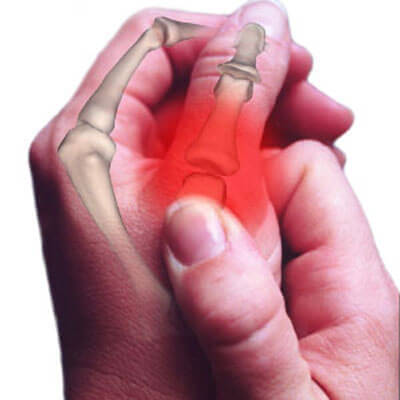

Parmaklarınızı, el ve ayak bileklerinizi ya da vücudunuzun herhangi bir bölümünü çıtlattığınız zaman duyduğunuz bu ses, eklemlerde bulunan sıvının içindeki baloncukların patlaması sonucu oluşur.

Eklemlerin kemikleri birleştiren noktalar olduğunu ve ince bir tabaka halinde “sinoviyal” sıvıyla kaplı olduğunu da unutmamak gerekir. Örneğin, bir parmak eklemini çıtlattığınızda, kütlettiğinizde ya da esnettiğinizde eklem uçları birbirinden ayrılır.

Eklemlerinizi saran kapsül esner ve genişler; böylece buradaki baskı azalır. Bu durum gerçekleştiğinde, sinoviyal sıvının içindeki gazlar baloncuk oluşmasına neden olur. Ardından baloncuklar söz konusu olan çıtlama sesini çıkartarak ‘patlar’.